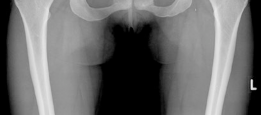

The radiographic evaluation of the dysplastic hip requires a highly standardized and rigorous protocol to accurately quantify the three-dimensional deformity. The initial assessment begins with a standing anteroposterior (AP) radiograph of the pelvis. In this patient, the AP view immediately reveals the hallmark signs of DDH: decreased anterolateral coverage of the femoral head and a broken Shenton line. The broken Shenton line—a step-off between the medial border of the femoral neck and the inferior border of the superior pubic ramus—indicates proximal and lateral migration of the femoral head due to structural instability. Furthermore, we observe an increased Tönnis angle (acetabular inclination) and a significantly reduced Lateral Center Edge Angle (LCEA) of Wiberg, confirming the diagnosis of severe lateral uncoverage.